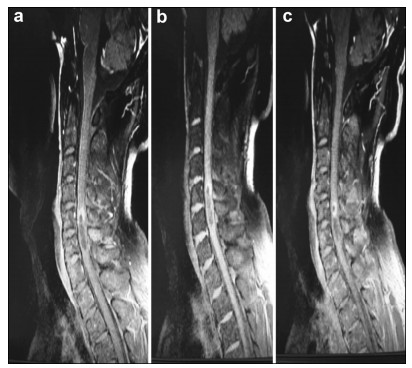

A 35-year-old male presented with the chief complaint of pain in the neck and back for 6 months. There was no weakness or numbness in the upper and lower limbs. MRI of the spine revealed an intramedullary mass at C5-T1. We advised resection. Because of cervical cord involvement, he underwent GTR under awake anesthesia (AAA), after providing informed consent. Intraoperatively, he was instructed to move his upper and lower limbs during the awake cycle of AAA. He was also not extubated during the awake cycle. All commands were followed. As the language center was not in the surgical field, no speech assessment was required. Sensory functions were also minimally assessed by lightly touching the upper and lower limbs and then asking the patient to raise his thumb if he perceived sensation. Frozen section confirmed the diagnosis of ependymoma, and GTR was performed successfully. His symptoms were completely relieved, and no motor deficits were observed at 3 and 6 months of follow up.

Preoperative and postoperative MR images of Case 2 are shown in Figure 3 and Figure 4, respectively.

| Figure 4 a–c. Postoperative MR images of Case 2. |